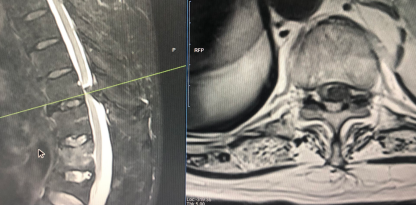

4、典型病例

昨日完成的一例胸椎黄韧带骨化症,椎管侵占率约80%,术中采用上述的分区椎板切除技术,完整切除骨化黄韧带和部分骨化硬膜,蛛网膜保持完整。